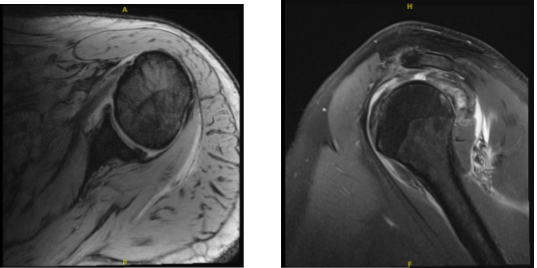

After performing an MRI, it was discovered that the left shoulder’s supraspinatus and infraspinatus were completely torn. Biceps tendon absence was also visible.

MRI-3T Left shoulder non-contrast